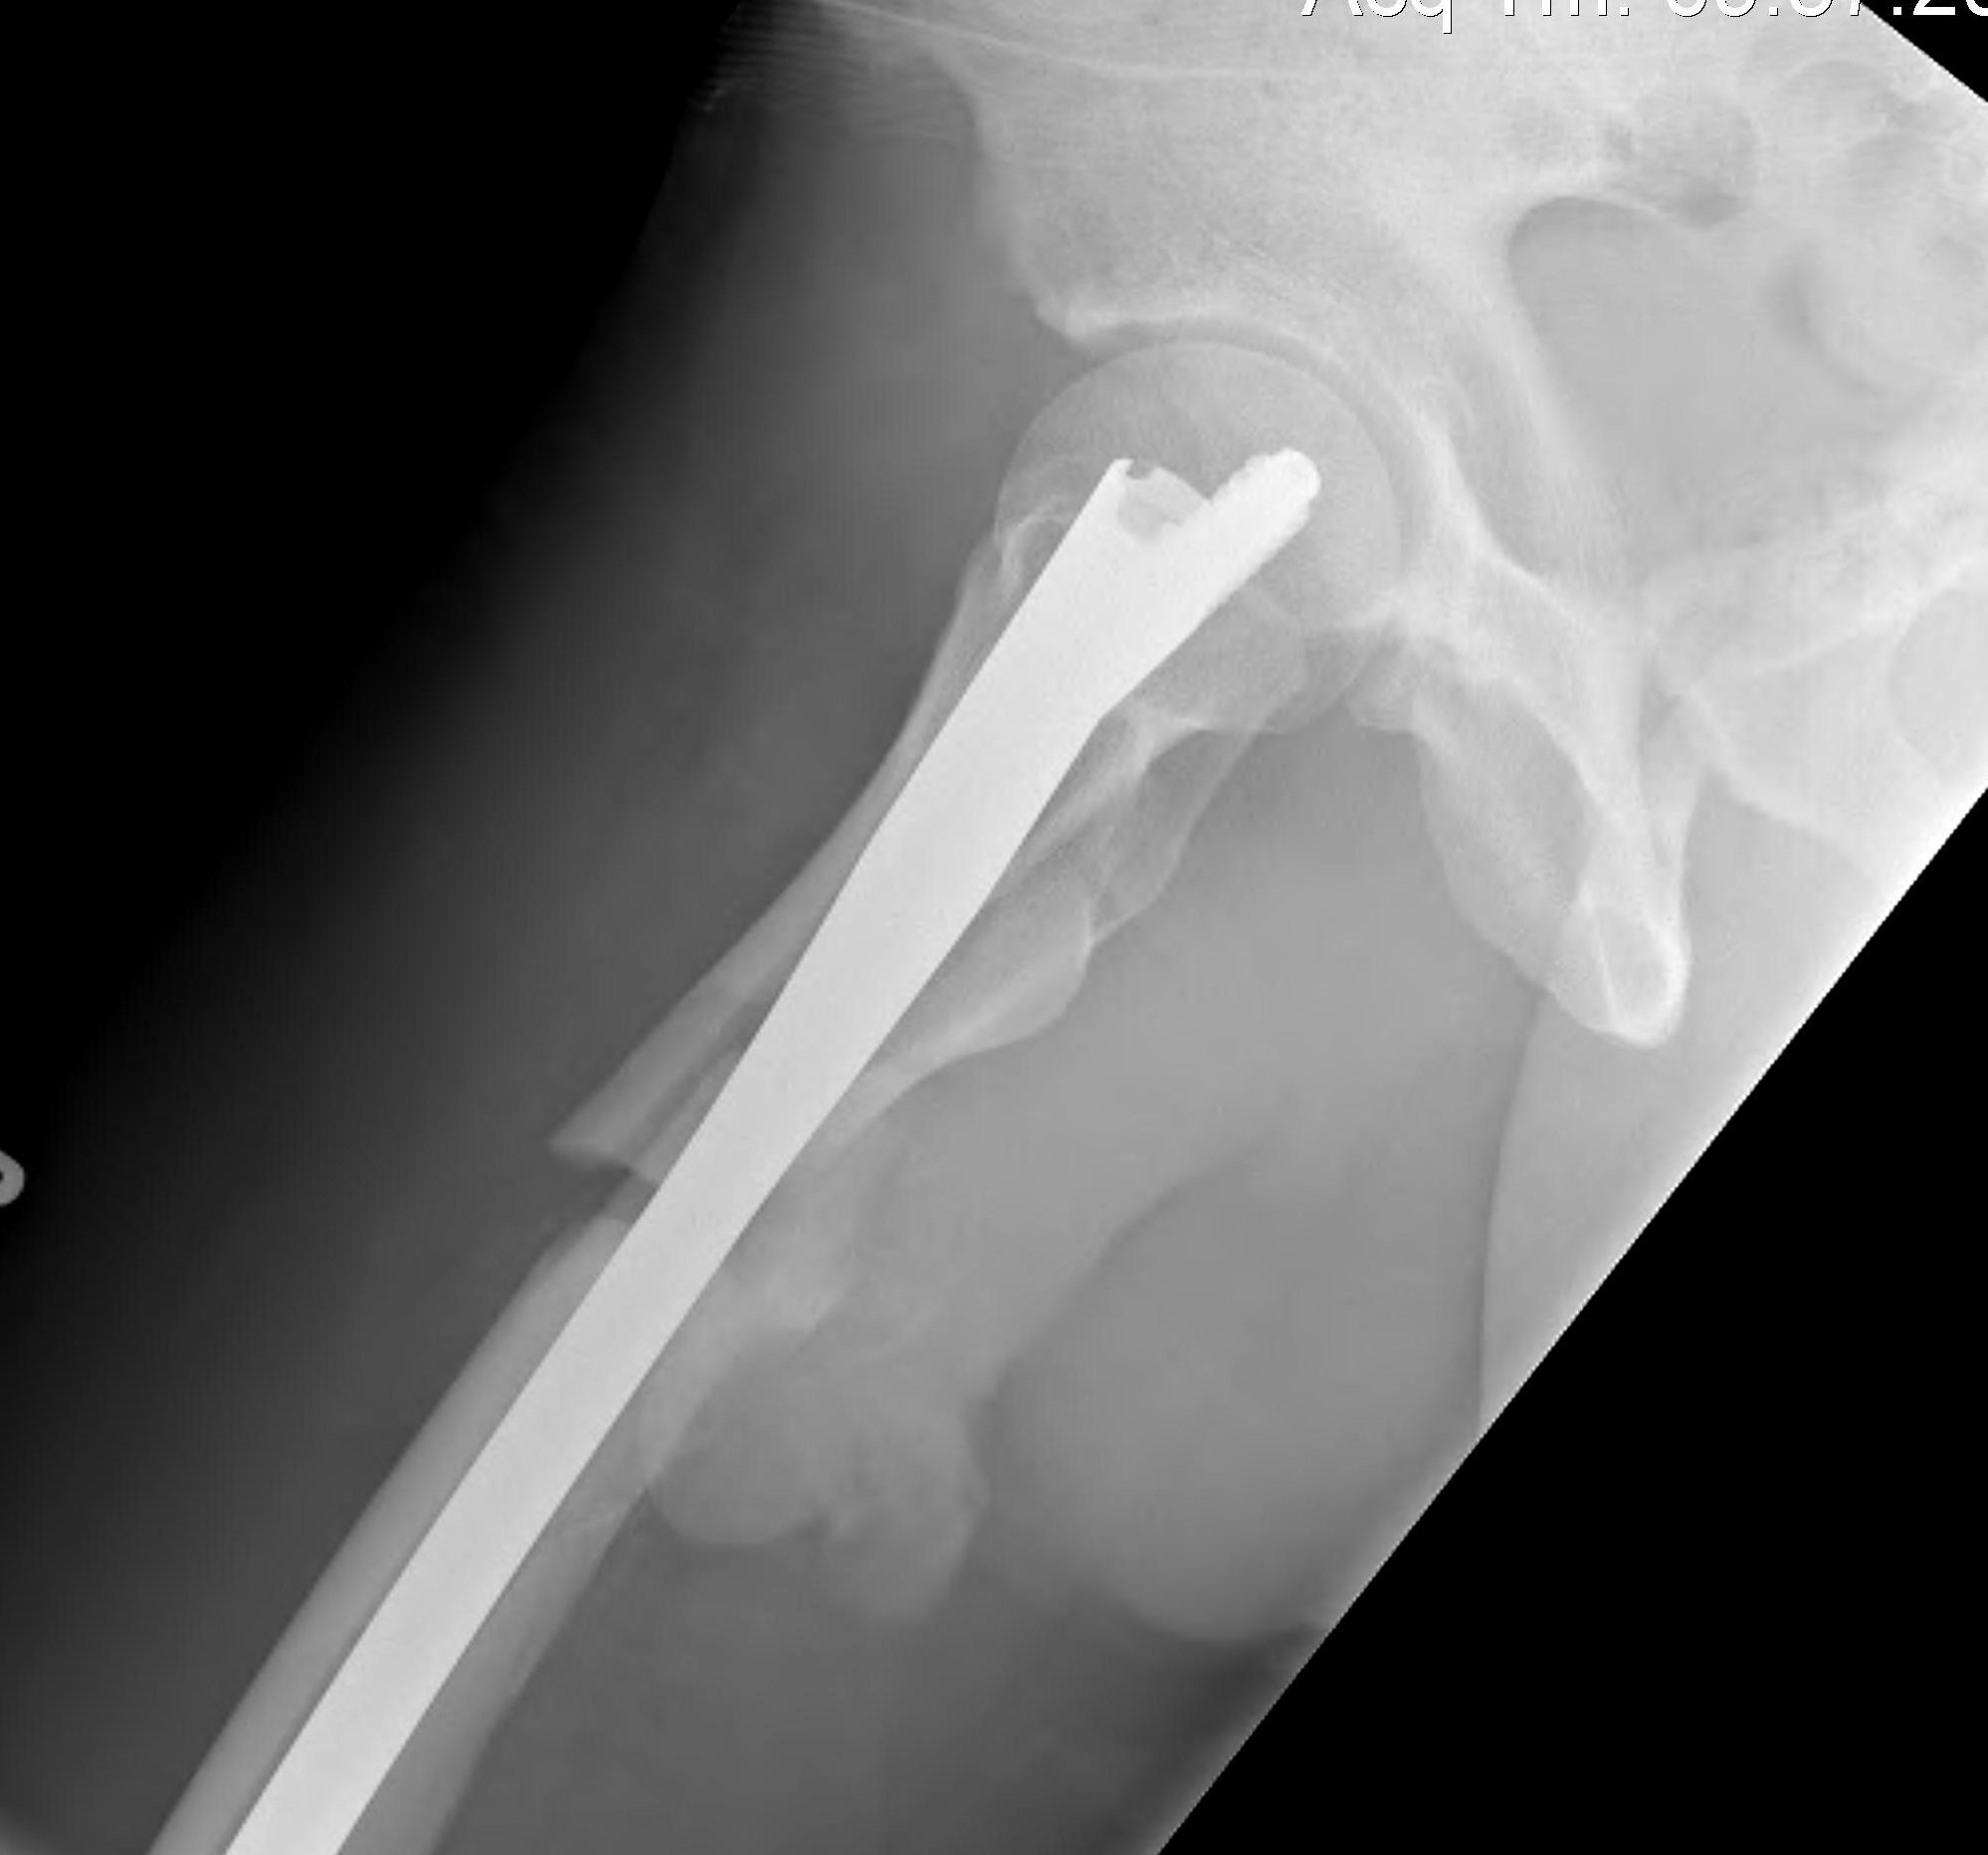

Fracture below lesser trochanter

Proximal 5 cm femoral shaft

1. Proximal fragment flexed, in varus and externally rotated with distal fragment adducted

- iliopsoas flexes proximal fragment

- abductors cause varus of proximal fragment

- external rotators rotate proximal fragment

- adductors medialize distal fragment